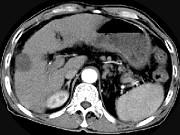

问题 男,63岁,肝区疼痛不适1个月,皮肤巩膜无黄染,AFP高于正常,CT所见如图,最可能的诊断是()

选项 A.肝血管瘤 B.肝转移瘤 C.阿米巴肝脓肿 D.不典型肝癌 E.胆管细胞癌

答案 D